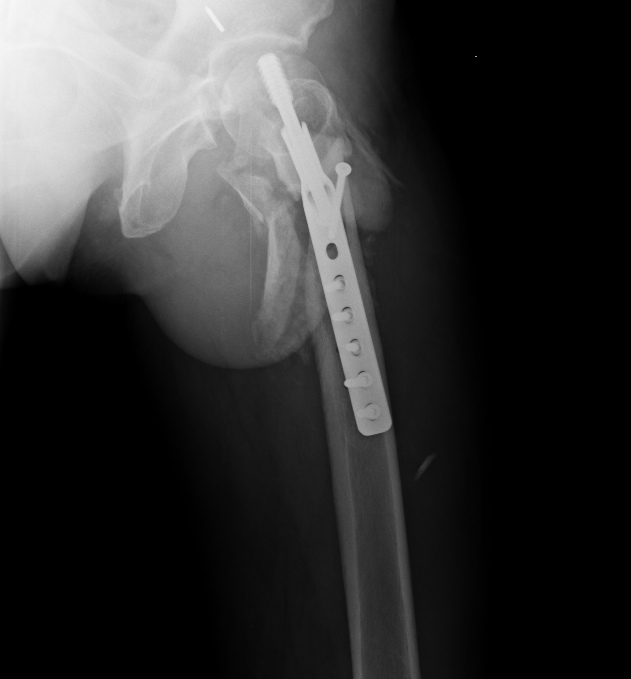

Мужчина 55 лет, оперирован полтора месяца назад в Прокопьевске.

Картина вот такая. Интересен еще и фрагмент спицы в вертлужной впадине. Ходит с костылями, не нагружая оперированную ногу.

Что будем делать? Оставить как есть и подождать? Клинковая пластина? Гвоздь? Сразу эндопротез? Что бы сделали?